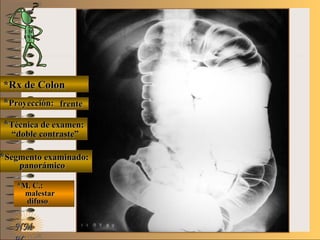

panorámicapanorámica

*M. C.:*M. C.:

sin clínicasin clínica

NMNM

BBAA CC

E ME M

UNTUNT

pacientepaciente

de piede pie

enen

decúbitodecúbito

dorsaldorsal

plieguespliegues

gástricosgástricos

áreasáreas

gástricasgástricas

volvervolver

*Rx de Estómago*Rx de Estómago

**Proyección:Proyección: